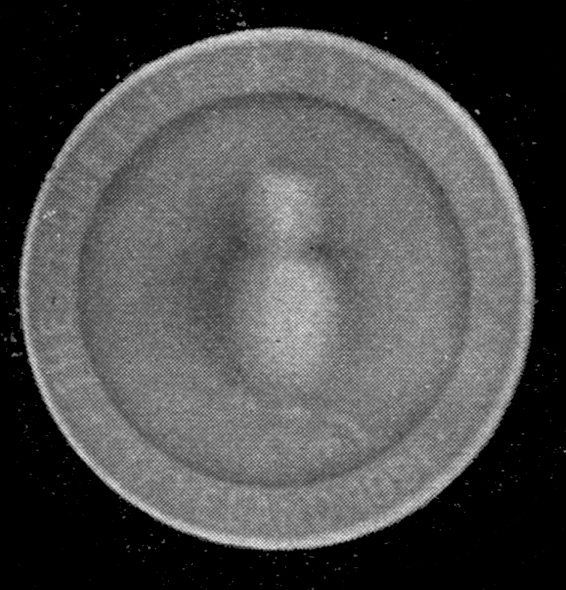

Fig. 1.—Head.